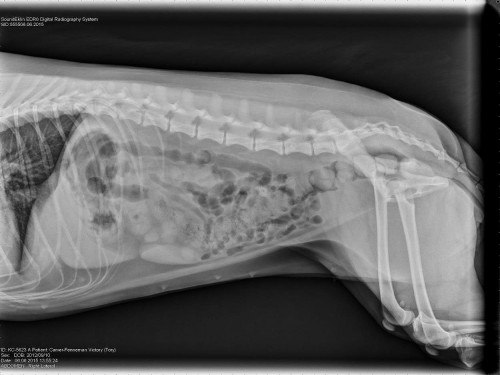

Victory’s urinary tract infection is back with a vengeance. We spent most of Saturday at the vet’s office, which required two visits to the vet in order to get a sterile urine sample. Fortunately, the vet was able to get a sterile urine sample (unlike last time), and we are awaiting the urine culture results in order to determining how to best treat Victory’s infection. In the interim, the vet did another exam and took an x-ray of our fur girl, shown below to check for abnormalities and stones. Fortunately, Victory’s insides look healthy; there are no bladder or kidney stones present; and her internal functions look good. The vet was able to easily review her x-ray because Victory is slender.

Victory is on another round of antibiotics along with this supplement. Part of Victory’s ‘lady parts’ are recessed, which may be contributing to her infections — a breeding ground for bacteria. We are going to clip furs and continue to use baby wipes to help keep her clean and everything hygienic around her ‘lady parts’ in the hope that this will help mitigate future infections. If the infections continue to occur frequently, the vet recommended possible surgery — we really hope never to reach this point. None of us were happy to be at the vet; however, Victory was really good and cooperative through it all.